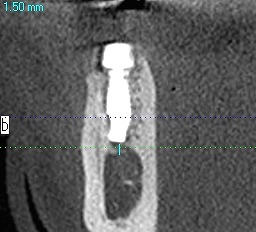

埋入後を見ていただくと距離もないことがわかります

10mmのインプラントでもギリギリのところかと思います

抜歯即時で行うと大穴が開いている状況なので、基準となる骨の位置が分かりにくいです

距離がないことがわかります

わずか1mm、2mmの世界の勝負なためいつもいい緊張感

にて行っています